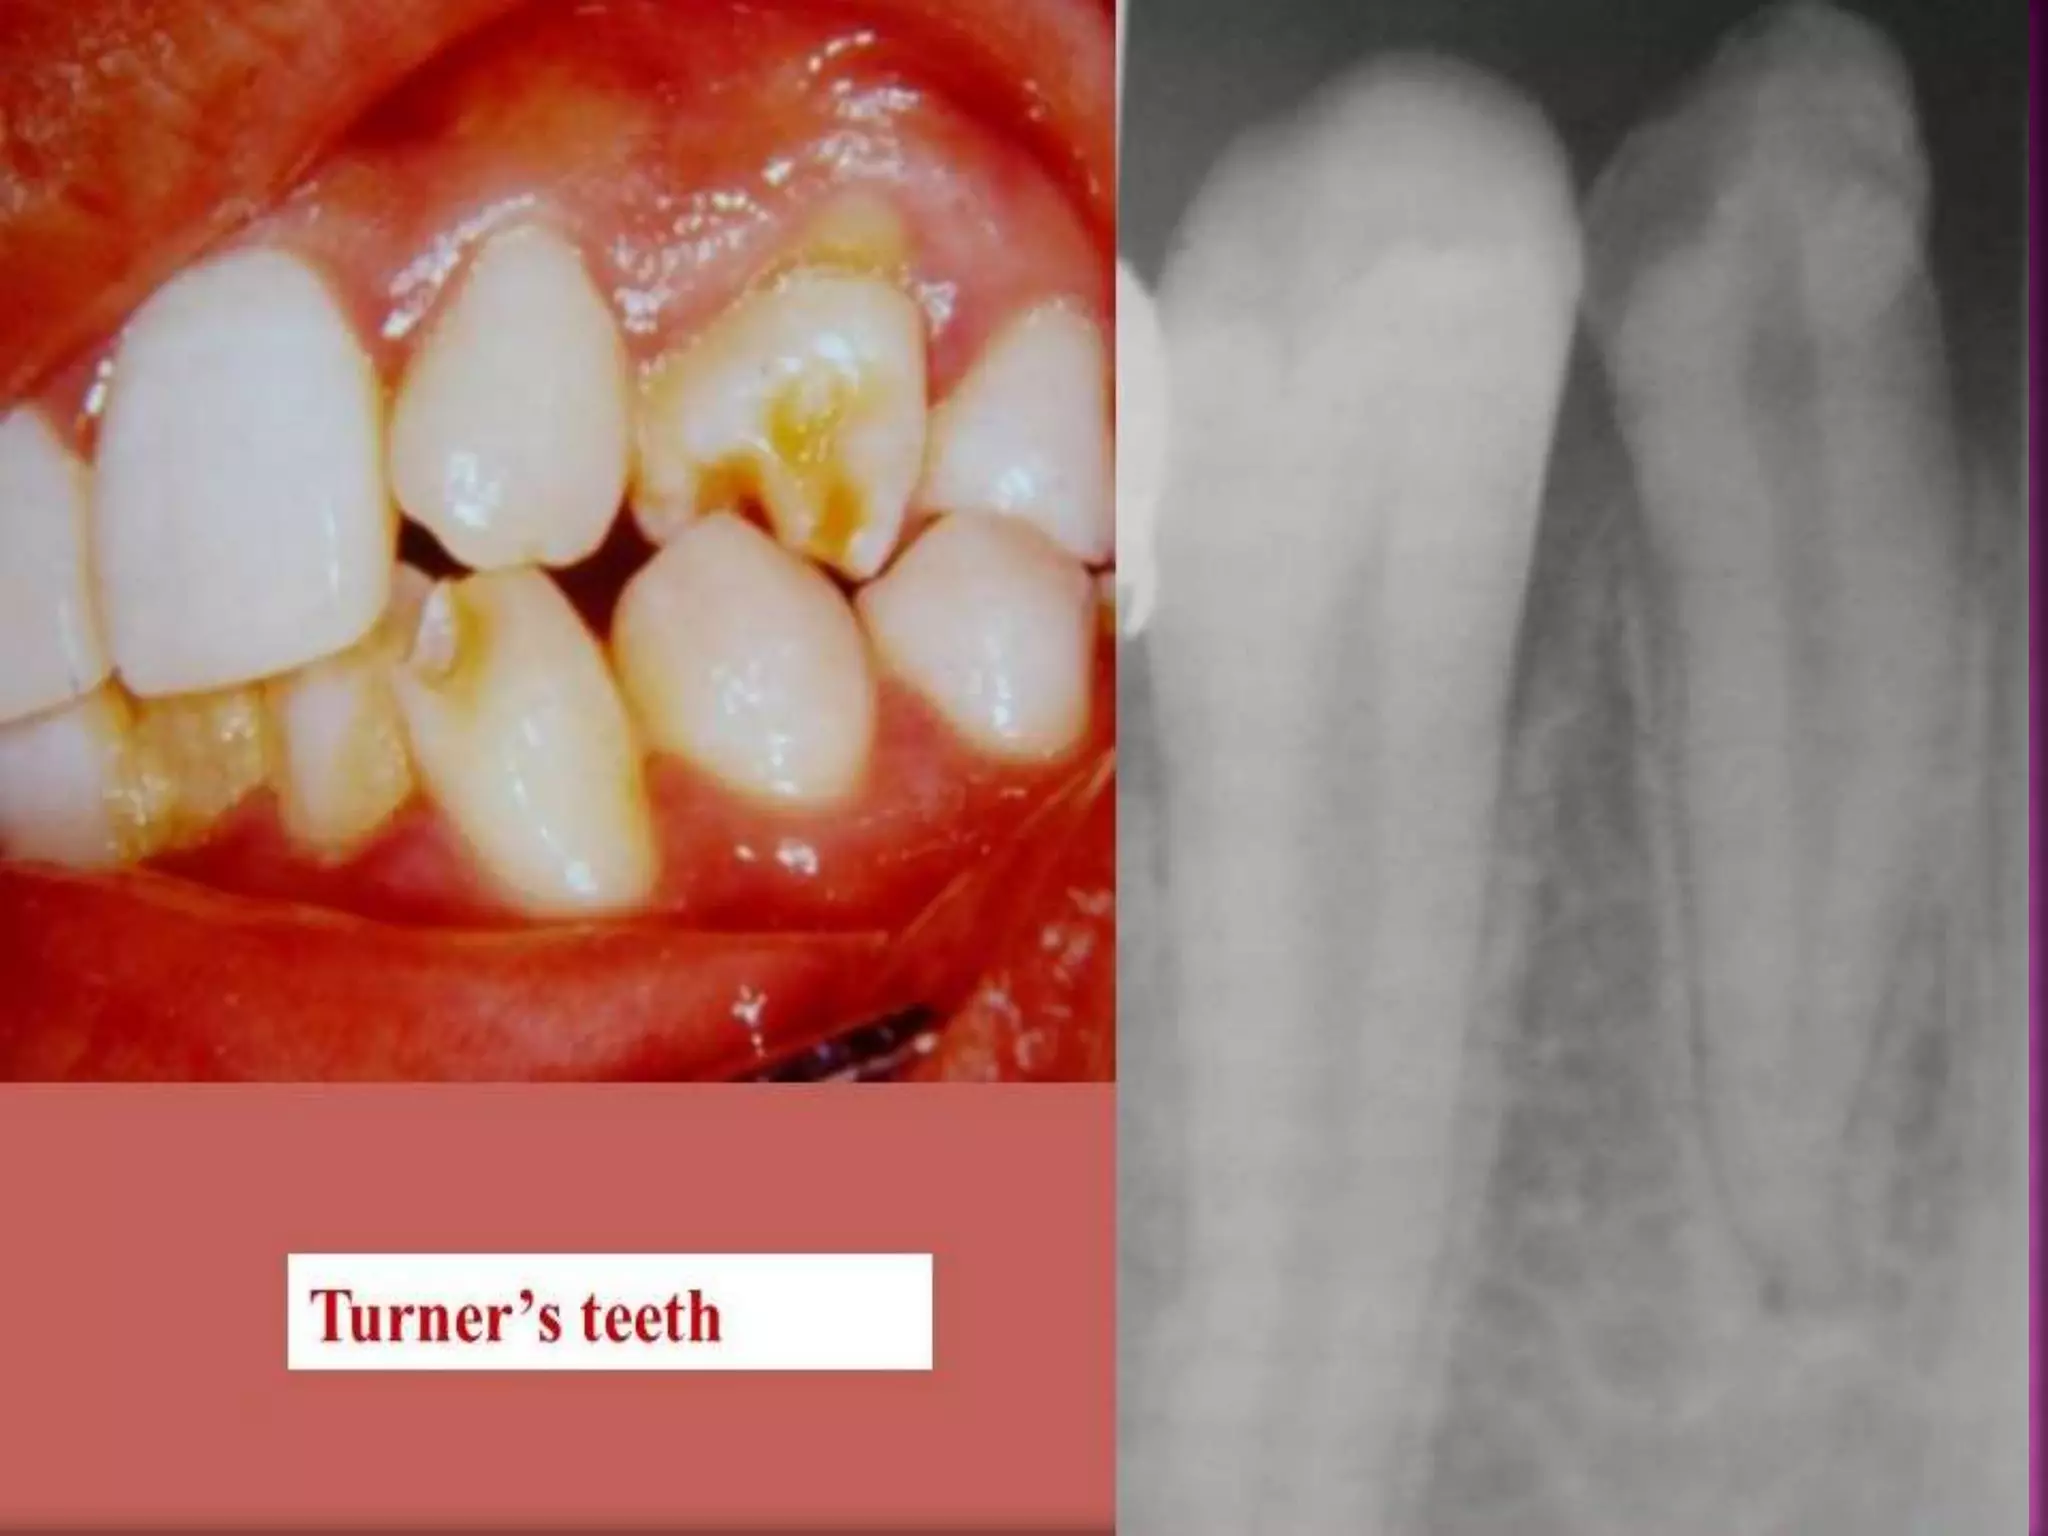

6. TURNER’S HYPOPLASIA-

 Turner’s Tooth- Localized type of hypoplasia, it

is caused by local infection or trauma and is

called as “Turner’s Hypoplasia” and the tooth

is called as Turner’s tooth.

 Pathogenesis-

A. Local infection- If deciduous teeth become

carious during the period when the crown of

succeeding permanent tooth is formed, then

bacterial infection involving periapical tissues

may occur and this may disturb the

ameloblastic layer of permanent tooth bud,

resulting in hypoplastic crown.

20

B. Trauma- When deciduous teeth have been

driven into alveolus and have disturbed the

permanent bud while the permanent tooth

bud is still being formed then resulting

injury leads to yellowish or brownish stains

of enamel usually on labial surface or as

true hypoplastic pitting effect.

 Site- Most commonly affected teeth are

permanent premolars as deciduous molars are

most frequently affected carious tooth in

primary dentition. lesion.

21

 Appearance- Hypoplasia may be ranging

from mild brownish discolouration of

enamel to severe pitting and irregularity of

crown. Cementum may also be stained

yellowish-brown.